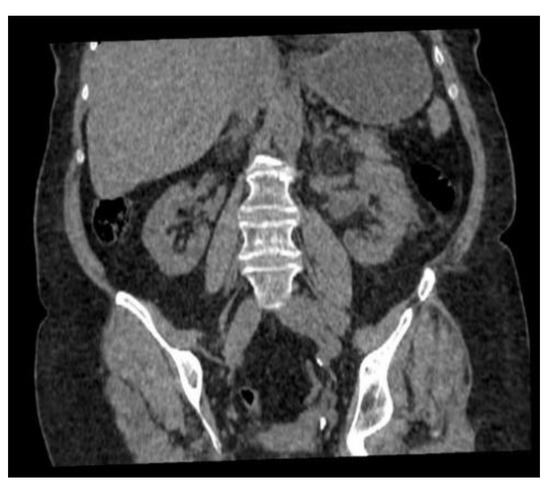

2. Case History